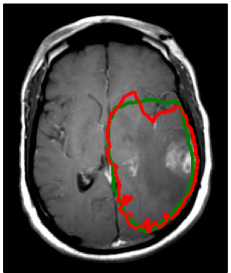

Refer to caption

Figure 5: (a) Log tumor cell density overlayed on the coronal T1 image showing spread of the tumor in the contralateral hemisphere (λw=4.2subscript𝜆𝑤4.2\lambda_{w}=4.2 mm and Dw/Dg=100subscript𝐷𝑤subscript𝐷𝑔100D_{w}/D_{g}=100). (b) Comparison of manual CTV (green) and model based CTV (red) (same contours as in figure 4.

In the manual delineation of the CTV used in the clinical plan, it is incorporated that the falx represents an anatomical barrier for the migration of tumor cells. Hence, the isotropic target expansion was trimmed manually. In the tumor growth model, the falx is modeled via a layer of CSF and is automatically accounted for through the assumption that tumor cells only migrate within white and gray matter. However, the corpus callosum connects the two hemispheres of the brain. The tumor growth model describes the migration of tumor cells through the corpus callosum (see figure 3 and 5a). As a consequence, the target volume based on the growth model is extended into the contralateral hemisphere. Figure 5a shows the tumor cell density overlaid on the coronal T1 gadolinium image. This illustrates the three-dimensional modeling of tumor spread via the model, including areas superior to the corpus callosum. This is not consistently accounted for in the manual CTV. In the manually drawn target volumes, the target is slightly extended into the contralateral hemisphere on the slices that show the corpus callosum, but not on the slices located superiorly and inferiorly (figure 5b). In the model derived target volumes, the target is extended further into the contralateral hemisphere, and the spread of tumor cells in superior-inferior direction beyond the corpus callosum is modeled.